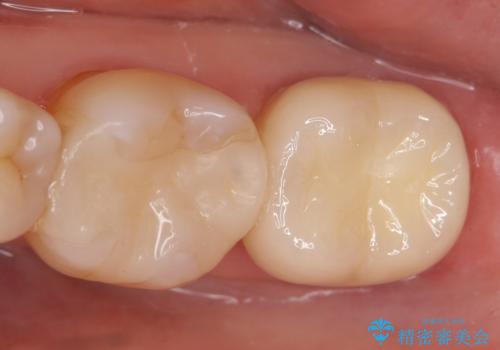

改めて再根管治療を行い、症状の緩解を確認後、オールセラミッククラウンによる補綴を行いました。

- オールセラミッククラウン…¥100,000、ファイバーコア…¥20,000費用は治療当時の料金となります

今回用いたオールセラミッククラウンはジルコニアフレームという白い素材の上にセラミックを盛っているため、審美性が非常に高いのが特徴です。

また、ジルコニアは人工ダイヤモンドの材料にも使われているほど高い強度を持っており、そのためオールセラミッククラウンは審美性だけでなく、奥歯やブリッジの補綴も可能とするクラウンです。